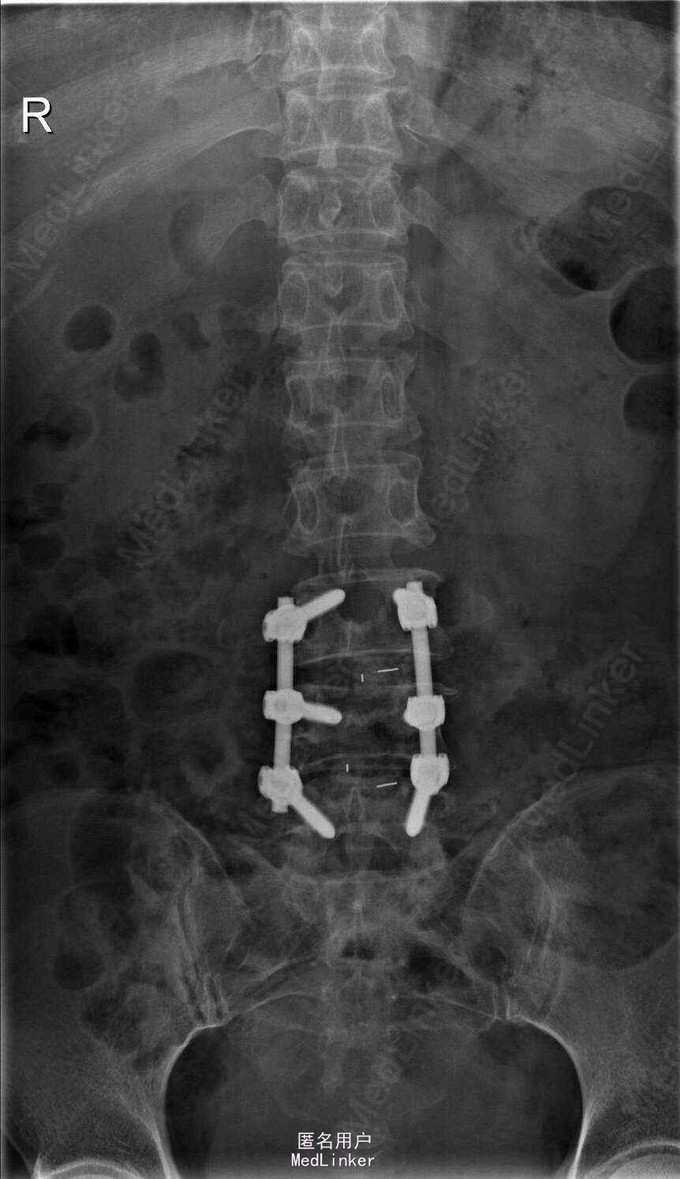

诊断:L3-4.L4-5椎间盘突出,椎管狭窄 治疗: 腰椎后路减压融合内固定术

术后麻木症状缓解,术后三月复查时,内固定装置位置良好,患者症状明显好转,行走后腰部稍酸胀,无腿部酸胀疼痛感。 讨论:外科病人术后随访较困难,病情好的较远的患者不再复诊,有何方法改善失访率?